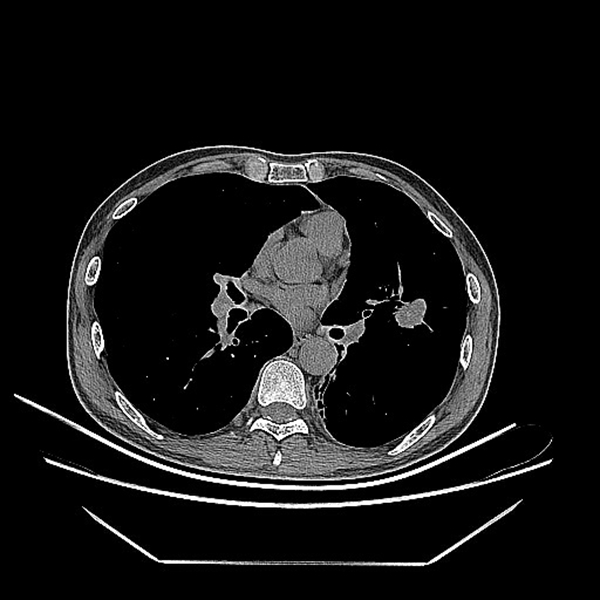

患者张某因体检发现左肺舌叶直径约2cm的结节而异常焦虑,希望能够尽快确诊病情进行积极诊治。但因其病灶在左肺舌叶第6-7级支气管水平,气管直径小,常规电子支气管镜难以到达,若是行CT引导下经皮肺穿刺,则需要穿破较多的肺组织,增加术中术后出血和气胸的风险;考虑到胸部CT提示心缘旁肿物,结合肺部占位,考虑肿瘤可能性大,直接行左肺舌叶手术切除,患者可能无明显获益。同时病区还有一例相似的患者。

面对诊治中的难点,科主任杨拴盈教授和主管医生张德信副教授、史红阳副教授、张永红主治医师经过详细论证后,决定选择电磁导航支气管镜进行肺部结节穿刺活检,先明确诊断。术前将患者的胸部CT资料导入3D智能重建系统中,生成患者的3D支气管树模型,并在电磁导航系统的引导下提前规划了手术路线,从而做到了术前成竹在胸。术中通过电磁导航系统的实时引导,按照既定路线可视化的快速到达了病变部位,完成了目标病灶的穿刺活检,ROSE提示有异常细胞,证明活检位置准确。操作全程仅用时不到20分钟,患者术后无咳嗽、咳血、胸痛等不良症状,身上未留下任何切口,次日即顺利出院等待病理结果。3日后,病理汇报两例分别为鳞状细胞高度不典型增生和肺腺癌。